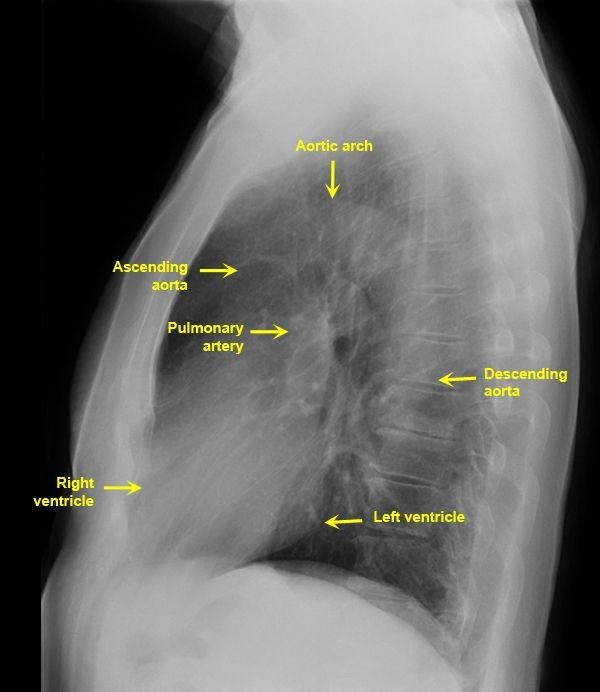

Lateral CXR

Left vent is posterior structure

Right vent is anterior and closest to chest wall

Clear space behind the sternum (solid white arrow)